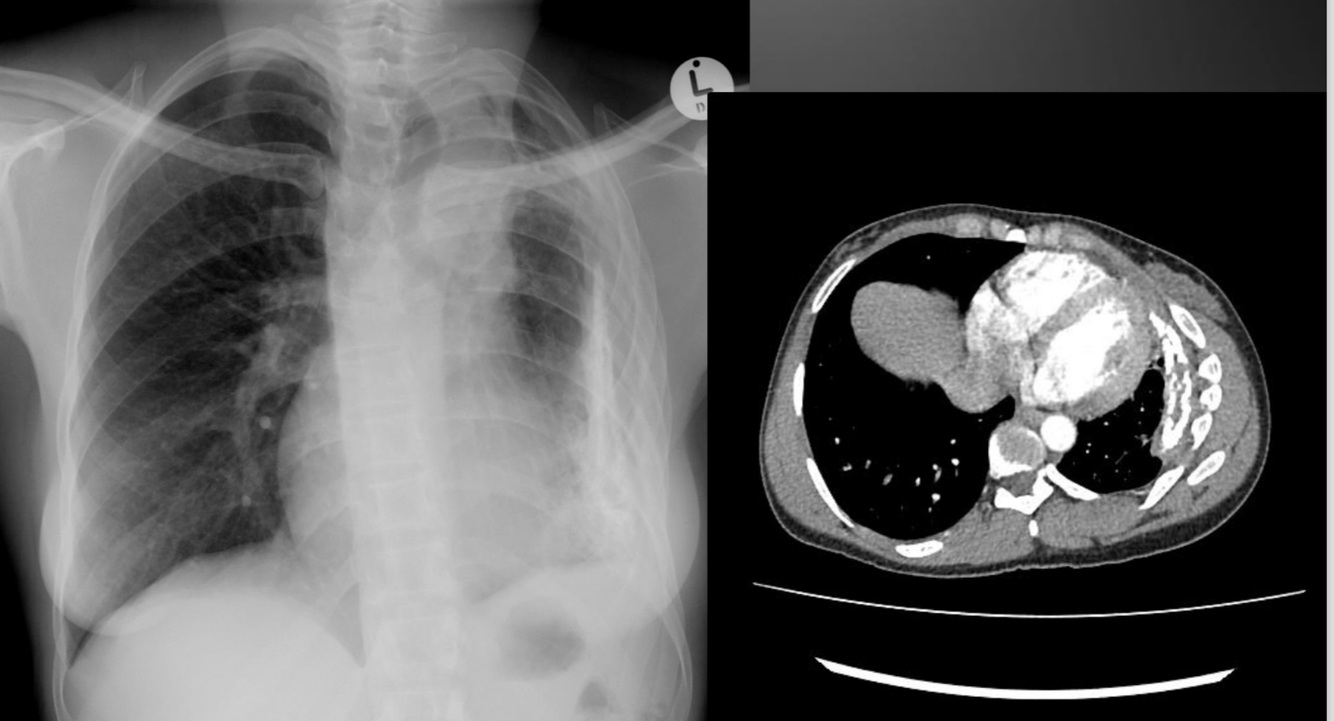

Pleural effusion (tb infected)

Post primary tb

A

Reactivation of latent infection or 2nd infection

SS: typical LOW, LOA, NS, fever, haemoptysis

Cavitation common, often apical and posterior segments

of lung, miliary spread, airway stenosis, SPN (occasionally)

Can be progressive

Post primary cavitation